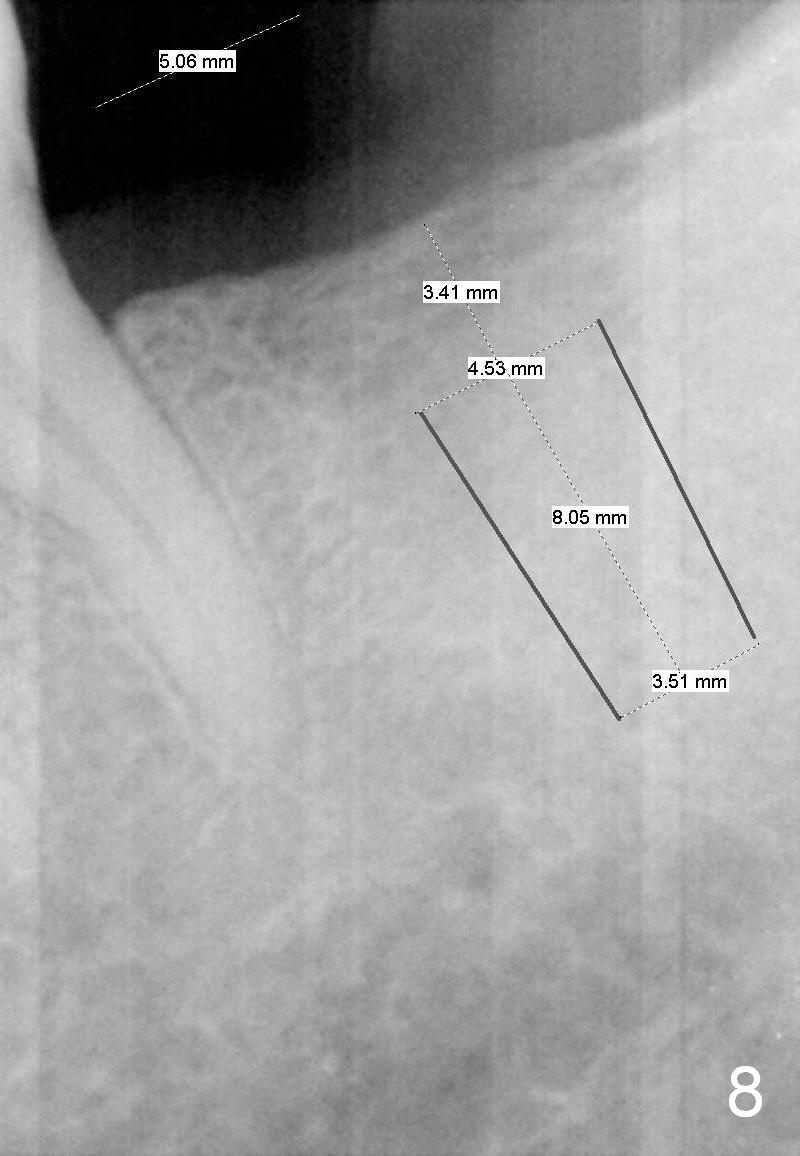

On second thought, Bicon implant is to be placed, either 4.5x8 or 5x6 mm (Fig.8).